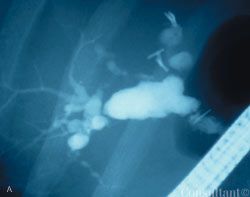

A 41-year-old man complained of upper abdominal pain and malaise of several months duration. He had emigrated to the United States from Korea 5 years earlier.